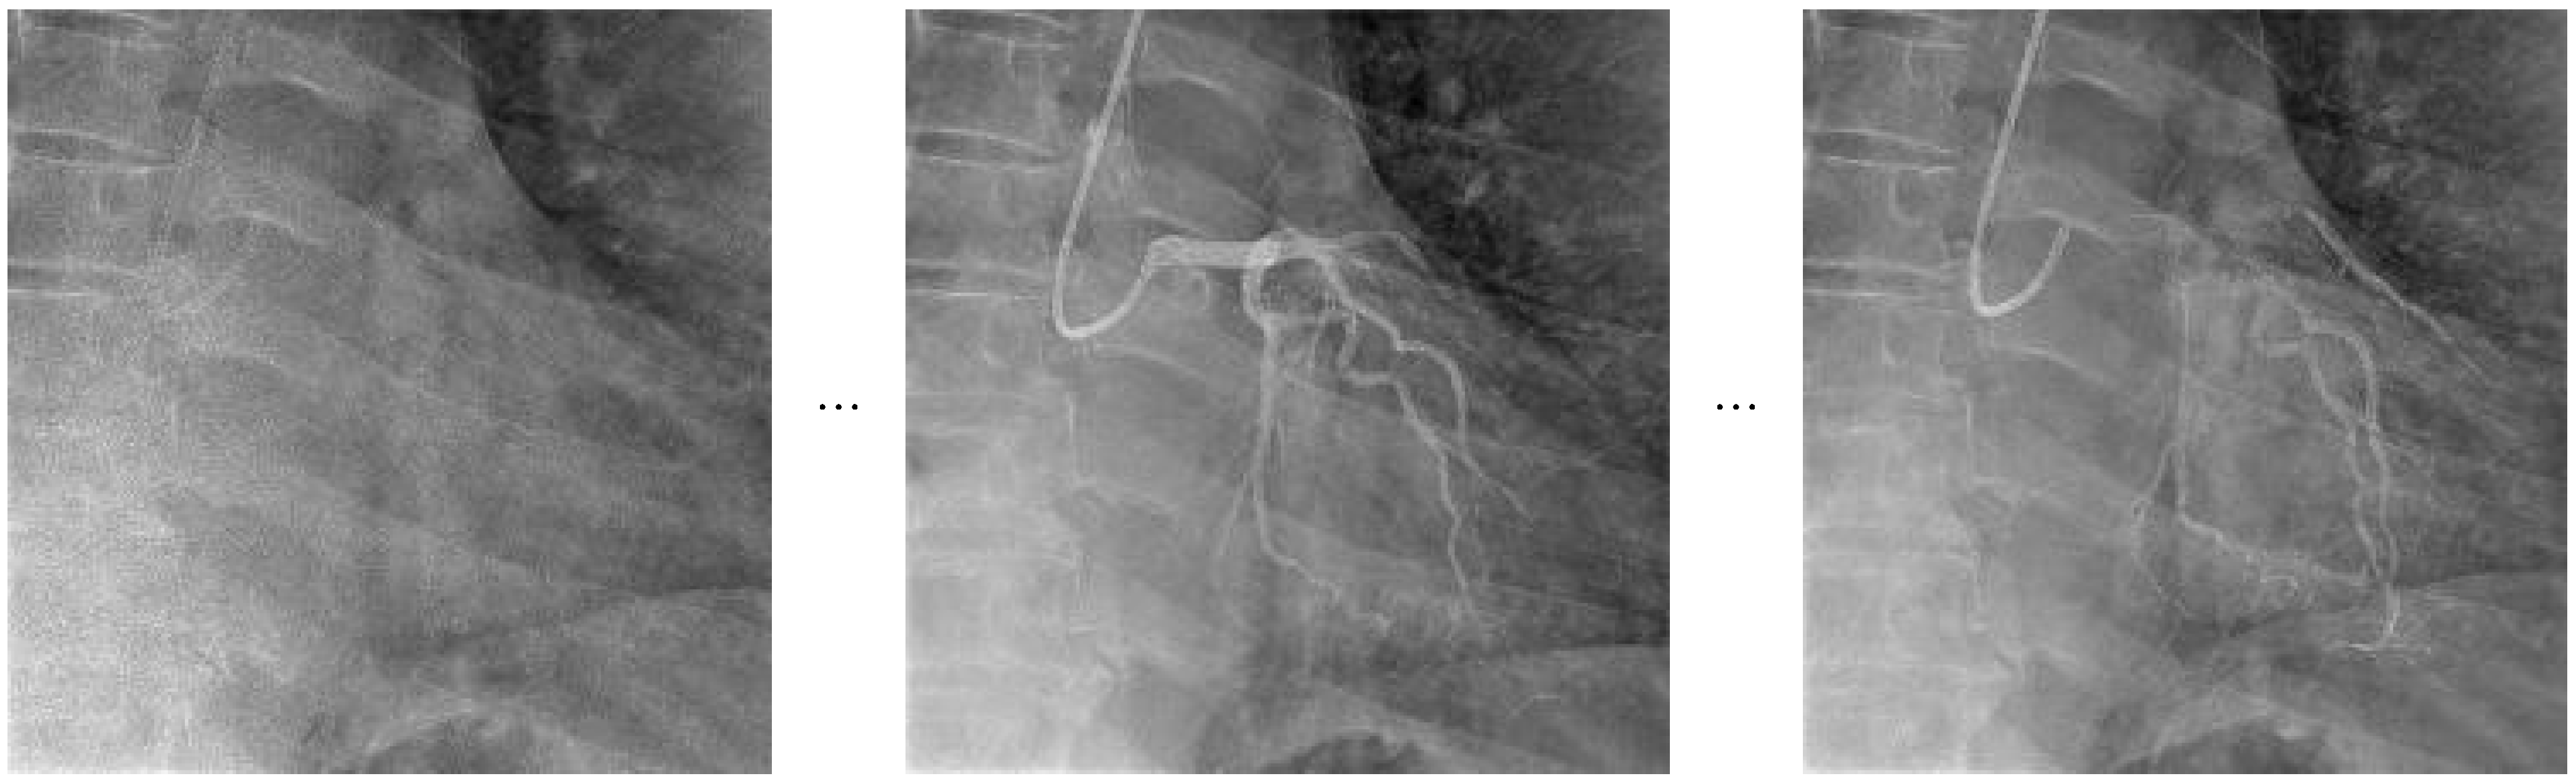

The overall architecture and operational concept of the VideoMAEv2 model, which is built upon a masked autoencoding framework and designed to learn spatiotemporal representations from video inputs, is depicted in Figure 5 for the task of video-based action recognition.

The frame sampling technique utilized in the Video Masked AutoEncoder V2 model, which selects temporally distributed frame segments to facilitate the reconstruction of masked video inputs, is visually presented in Figure 6.